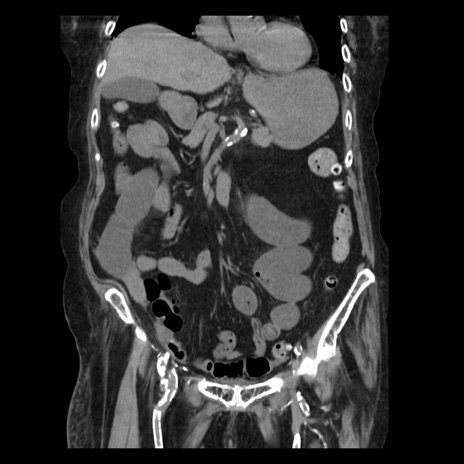

症例14(冠状断像)

【症例】 90歳代女性

【主訴】 腹痛・嘔吐

【現病歴】今朝から左側腹部痛を認めた。 経過観察していたが、嘔吐を認めたため来院。

【既往歴】 子宮癌術後

【身体所見】 意識清明、BP 127/54mmHg、P 98bpm Sp02 95%(RA)、BT 35.8°C、腹部平坦・軟腸ぜん動音聴取良好、右下腹部圧痛(+) 反跳痛なし

【データ】WBC 9800、CRP 0.46